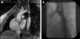

Small aorta syndrome

Aorticoiliac steno-occlusion